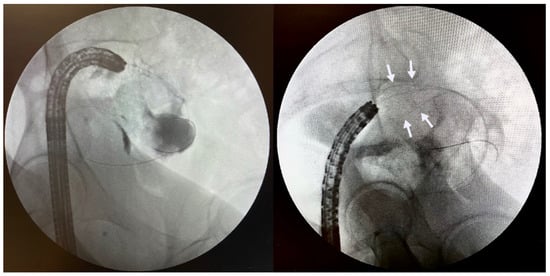

5.4. Endoscopic Gastroenterostomy

6.2. Gastroduodenal